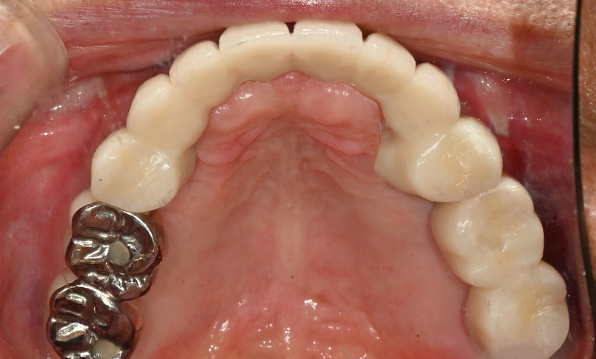

잇몸뼈 충분히 이식 후 임플란트 식립

성공을 위한 노하우, 잇몸뼈 재건 기술

이 때, 치조골 이식을 병행하여 잇몸뼈 재건 후 안정적인 임플란트 식립을 하고 있습니다.

치료기간 : 2021.04.12~2021.09.15